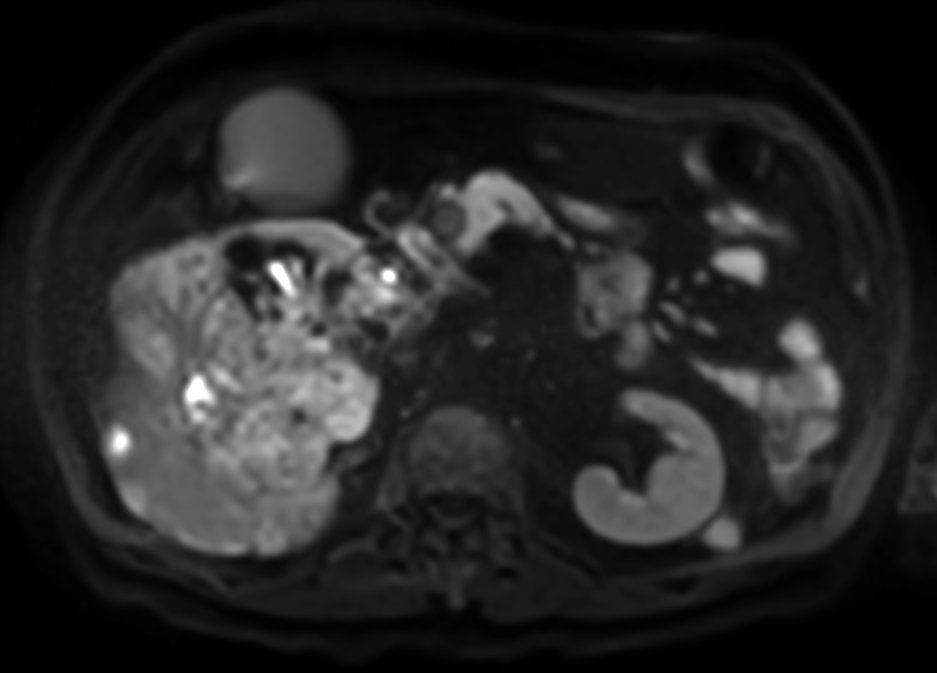

Patient with kidney tumor. ExamCard includes Compressed SENSE to shorten the breath hold time, VitalEye for touchless respiratory sensing, mDIXON XD FFE to acquire up to four image types in one single scan, DWIBS to achieve high contrast between background and lesions and bTRANCE for non-contrast time-resolved imaging.

DWI (b50)

DWI (b400)

DWI (b800)

DWI (ADC)

DWIBS